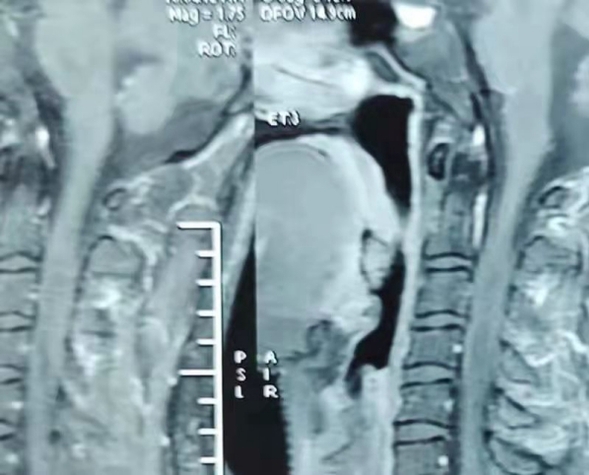

患者,男,26岁,因右上肢活动受限2月入院治疗。颈椎核磁平扫及强化检查明确有颈段髓内占位性病变(颈2-颈5)。

术前核磁强化